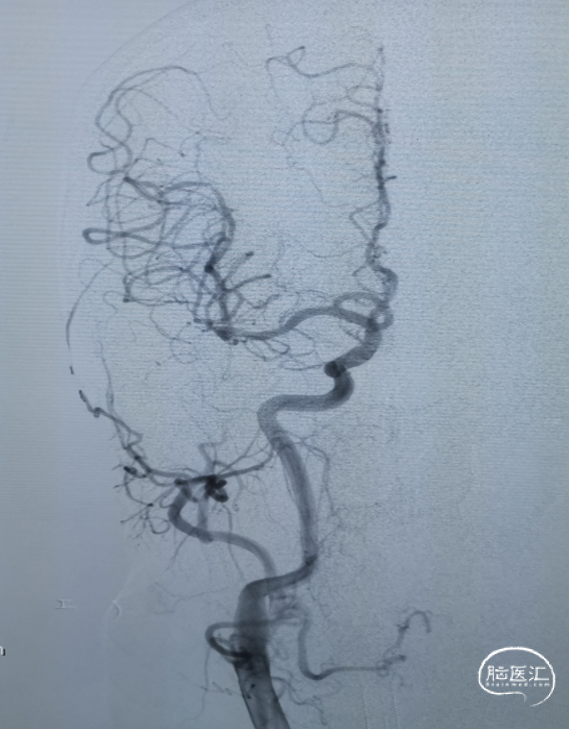

右侧颈动脉造影未见向左侧代偿。

左侧颈动脉造影提示左侧颈内动脉末端闭塞。